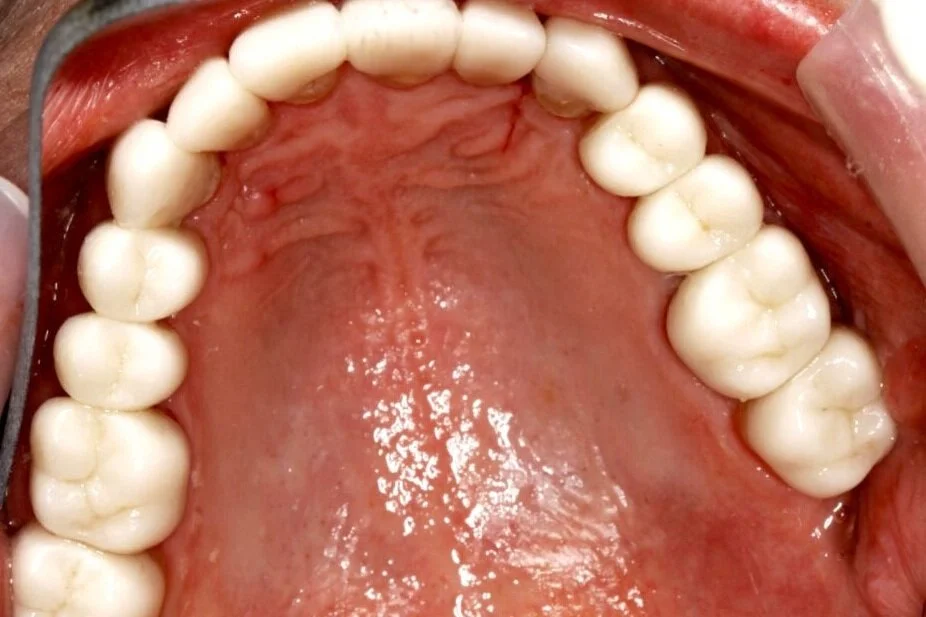

Gallery Dental Designs Roseville, CA Teeth Whitening Roseville Professional dental services in roseville, ca and greater sacramento area. Teeth whitening, root canals, cosmetic dentistry, implants and more. Whitening in roseville, lincoln, and neighboring areas. Teeth whitening is a cosmetic dental procedure designed to lighten the color of your teeth and remove stains and discoloration. If you want to enhance your smile's appearance, professional teeth whitening may be the. Teeth Whitening Roseville.